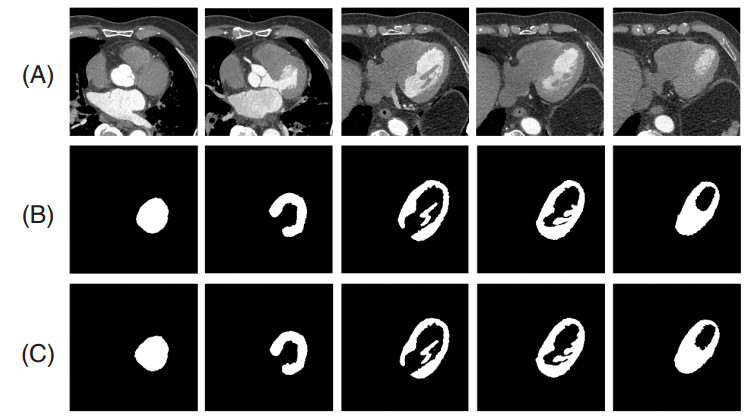

图 3展示了一例患者的5幅CT左心室图像及其相应的分割结果,表 1给出了本文方法分割CT左心室的评估结果。可以看出,本文方法对于CT左心室具有较高的分割精度。其中,Dice=95.20%、IoU=92.12%表明分割得到的左心室区域和标准的左心室区域的空间重合度较高,精确度为97.45%表明分割得到的左心室区域中标准区域占的比重较高,敏感度为94.45%表明分割左心室区域的能力较强。

| (A):原图;(B):金标准;(C):本文方法的分割结果 图 3 一例患者的5幅左心室图像及其相应的分割结果 |